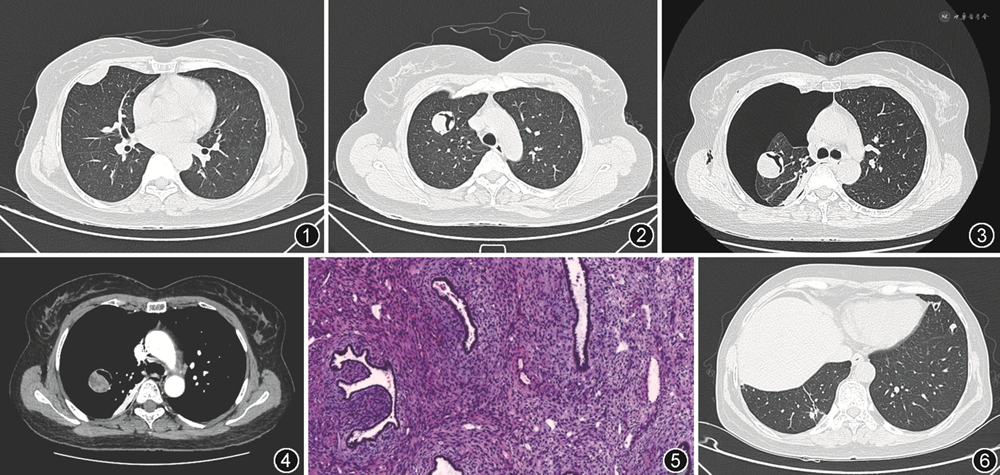

1年前胸部CT示双肺多发类圆形软组织密度肿块影,边界光整,内见裂隙样气体影,胸膜下亦见多发扁平状软组织密度影,密度较均匀,边界清晰(图1,2)。本次CT示右侧气胸,肺组织压缩约80%,压缩肺组织内多发软组织密度占位,部分结节内可见裂隙样气体密度影,边界均较清晰、光滑,增强后病灶实性部分明显强化,内部见多发小片状低强化或未强化区,无出血或钙化(图3,4)。影像诊断:考虑良性病变,但不能完全排除转移瘤。遂患者接受胸腔镜下右肺肿物楔形切除术,术中见右肺发育正常,肺裂发育可,右肺中叶内侧段肺大泡形成。其中右肺上叶前段肿物大小约4 cm×3 cm,右肺中叶内侧段肿物大小约4 cm×3 cm,外侧段肿物大小约1 cm×1 cm,右肺下叶外基底段肿物大小约1.0 cm×1.5 cm,右肺下叶后基底段肿物大小约1 cm×1 cm,各肿物呈类圆形,边界清晰,质中,色灰白。术中直视联合手指触摸明确结节位置并逐个完整切除。术后病理:(右肺肿物)呈结节状,边界清晰,由梭形细胞构成(图5),无明显异型性及核分裂象。免疫组化:CK(+),EMA(肿瘤上皮+),TTF-1(肿瘤上皮+),h-caldesmon(-),ER(肿瘤间叶+),PR(肿瘤间叶+),Ki-67(+,5%),SMA(-),Desmin(肿瘤间叶少量+),Myogenin(-),S-100(-),CD99(-),CD56(-),Bcl-2(-),Vimentin(肿瘤间叶+)。病理诊断多发性纤维腺瘤(pulmonary adenomyoma,PAM)。患者术后1年随访影像示左肺结节出现含气腔隙影(图6)。

PAM在组织学上属于梭形细胞为主的良性肿瘤,常表现为密度均匀、边界清晰、无出血或钙化征象的均质性结节或肿块,不表现出对周围组织的侵袭或远处转移,术后无复发。关于PAM多为个案报道,且多集中讨论病理诊断和分析[2, 3, 4],相关影像学研究罕见。结合目前文献报道[2],PAM通常发生于胸膜下区,亦可发生于心膈角区,单发为主,多发十分少见,左肺多于右肺,病变直径多较小或中等,直径0.5~2.7 cm,边界清晰,增强扫描强化均匀明显。多发PAM十分少见,国内报道的多发PAM仅有1例[3]。该例患者影像表现为双肺多发占位,胸膜下及肺内均可见,右肺病变明显多于左肺。文献报道PAM多为均匀实性密度,而本例患者多个病灶内出现裂隙状气体,文献中尚未见到此种征象报道,且随访中发现起初完全为实性的结节中出现了含气腔隙,病理上也可见到多发的裂隙状腔隙,内部是气体,表面被覆肺泡上皮,无明显异型性,是否与病变好发于胸膜下区一样,提示病变起源于肺实质外的间质组织[5],围绕肺泡生长导致肺泡口堵塞,引起肺泡积气,形成裂隙样含气改变,尚需要更多病例积累。本例患者出现气胸后,胸膜下病灶跟随肺组织一同回缩,并不黏附于胸膜,更加支持PAM是起源于肺内间质,而不是肺外组织的结论。